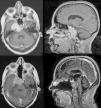

ResultadosCatorce pacientes (hombre/mujer 2:1) con una media de edad de 49años en los cordomas y de 32años en los condrosarcomas. La presentación clínica más frecuente fue la diplopía (78,5% de los casos), seguida de la disfagia (28,6%). Histológicamente se reportaron como cordomas el 71,4% y como condrosarcomas el 28,6%. Además, se encontró en el 81% de los casos invasión de al menos dos o más tercios del clivus, en el 57,1% invasión intradural y en el 35,7% invasión sellar. En el 42,8% de los casos el grado de resección fue total y en el 21,5%, subtotal. La complicación más frecuente fue la fístula de LCR, que se presentó en el 28,6% de los casos, habiendo que intervenir solo a un paciente. En el 35,7% de los casos se indicó tratamiento coadyuvante con Proton Beam y en el 21,5% radioterapia convencional. La media de seguimiento fue de 53,5meses, y se encontró recurrencia o progresión tumoral en el 21,5% de los casos, dos de los cuales no había recibido coadyuvancia. No hubo fallecimientos.

ResultsWe had fourteen patients (male/female 2:1), with a mean age of 49years for chordoma and 32 for chondrosarcoma. The most common clinical presentation was diplopia in 78.5% of cases, followed by dysphagia in 28.6%. Histologically, 71.4% were chordomas and 28.6% were chondrosarcomas. In addition, invasion of at least two thirds or more of the clivus was found in 81% of the cases; in 57.1% there was intradural invasion, and in 35.7% invasion of the sella turcica. In 42.8% of cases, the degree of resection was total and in 21.5% subtotal. The most common complication was CSF fistula, occurring in 28.6% of the cases, with only one case requiring surgery to repair it. Adjuvant treatment with Proton Beam was performed in 35.7% of cases and with conventional radiotherapy in 21.5%. Mean follow-up was 53.5months and tumour recurrence or progression was found in 21.5% of the cases, two of which had not received adjuvant treatment. There were no deaths.